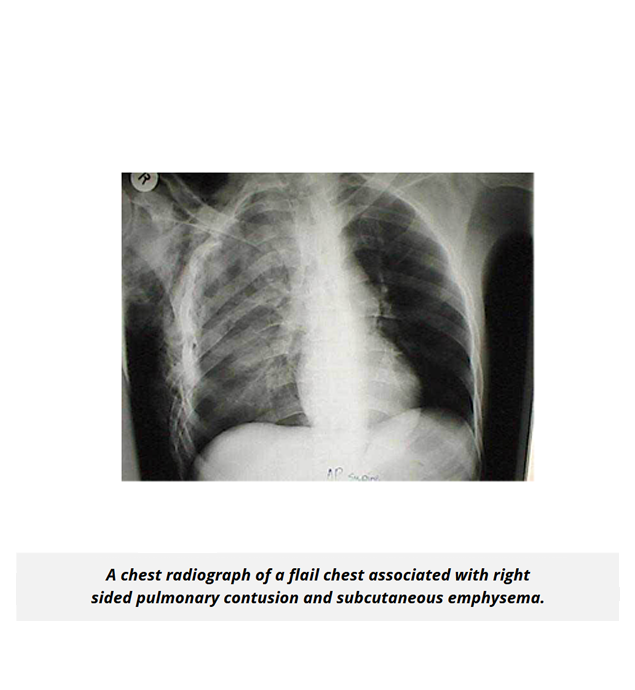

The UMock USMLE® Step 1 prep course features high quality pathologic images, gross and microscopic views, as well as radiologic imaging illustrating key concepts, disorders, and abnormal processes to help you gain a complete understanding of subject material.

Respiratory System Content Review 9% - 13%

The UMock USMLE® Step 1 prep course provides a condensed, high-yield review of concepts to help you fully understand normal and abnormal pulmonary processes, and how to apply knowledge to clinical scenarios relating to pathologies that affect the lungs, pulmonary function tests, ventilation/perfusion mismatch, and cell types and their function based on their location in the respiratory tract.

The course includes volume calculations as well as high quality graphs and diagrams to help you learn exactly what is tested from each topic, and how to apply it to respiratory medicine.